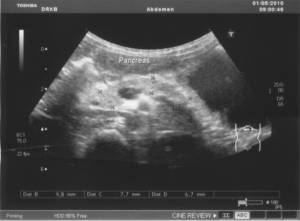

Рис.4.6. Эхограмма поджелудочной железы ребенка 6 лет.

Значительное повышение эхогенности поджелудочной железы. Контуры нечеткие,

неровные

Ультразвуковое исследование проводится утром, натощак.

Поджелудочная железа размеры натощак: головка 9,4 мм,

тело 7,0 мм, хвост 6,5 мм., гиперэхогенная, контуры нечеткие, неоднородная с

гиперэхогенными участками в области тела и хвоста (кисты?). Диаметр селезеночной

вены 3,2 мм, скорость линейного

кровотока 0,27 м/сек, объёмная скорость кровотока 0,12 л/мин.

Поджелудочная железа постпрандиально: головка 9,8 мм.,

тело 7,7 мм., хвост 6,7 мм. Диаметр селезеночной вены 3,4 мм, скорость линейного кровотока 0,33 м/сек,

объёмная скорость кровотока 0,17 л/мин.

Заключение:

размеры поджелудочной железы уменьшеумны, кисты в области тела и хвоста.

Диаметр СВ уменьшен, ЛСК и ОСК снижены.